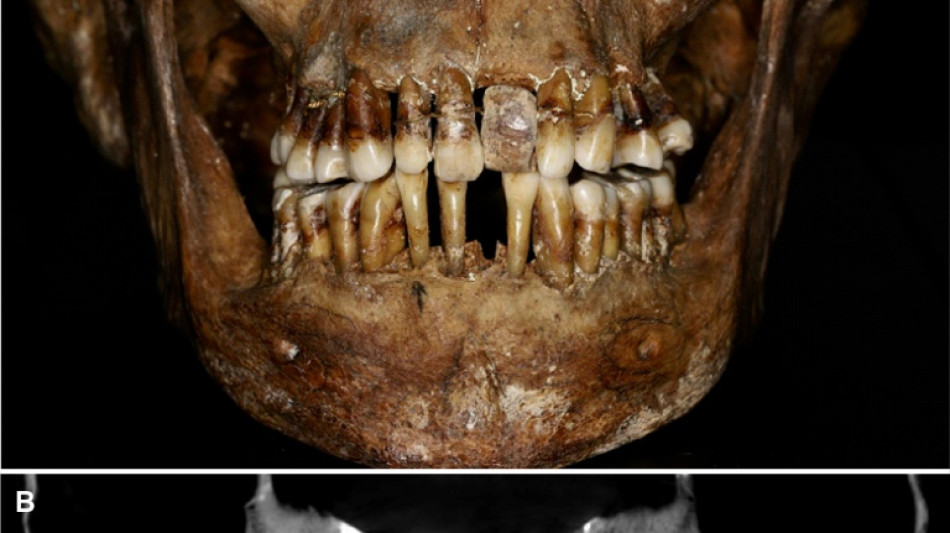

La dentition d'une aristocrate du XVIIe siècle comme marqueur social / Photo: Handout - INRAP/AFP

La sépulture d'Anne d'Alègre, morte en 1619 à l'âge de 54 ans, avait été déterrée lors d'une fouille au château de Laval, en 1988. Embaumé dans un cercueil de plomb, le squelette était particulièrement bien conservé, sa dentition aussi.

Plus de trente ans après, une équipe comprenant des archéologues et des dentistes dévoile qu'Anne d'Alègre était atteinte d'une maladie parodontale qui provoque le déchaussement progressif des dents, selon une étude parue cette semaine dans Journal of Archeological Science.

Les images radiologiques par "Cone Beam", un scanner en 3D, montrent que la patiente portait une prothèse dentaire remplaçant une incisive, soutenue par des fils d'or, ainsi qu'une ligature de contention sur des pré-molaires.

Des examens en macroscopie ont déterminé que cette prothèse était en ivoire d'éléphant, écartant la piste de l'ivoire de dents d'hippopotame, également utilisé à l'époque.

Ce traitement n'a fait "qu'aggraver la situation" de la patiente, explique à l'AFP Rozenn Colleter de l'Inrap (Institut national des recherches archéologiques préventives), auteure principale de l'étude.

A long terme, ce traitement, ainsi que les "multiples resserrages nécessaires, ont entraîné l'instabilité des dents voisines", détaille l'Inrap.

La révélation de sa pathologie dentaire "montre qu'elle a subi beaucoup de stress" au cours de cette période troublée de l'histoire, souligne la chercheuse, selon laquelle cette étude est "un peu une manière de la réhabiliter". Anne d'Alègre a dû d'autant plus souffrir qu'elle a porté sa prothèse plusieurs années, et que les soins n'étaient pas prodigués par des dentistes professionnels.